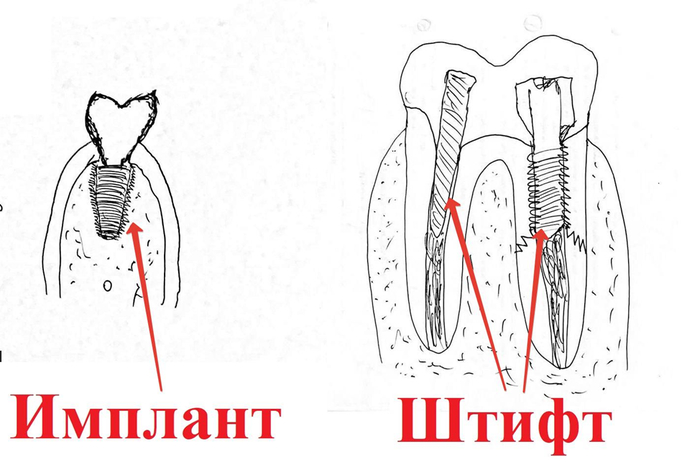

Перед детальным разбором всего этого дела, хотелось бы всех предостеречь от подмены понятий.

Штифт-это инородное тело, которое вставляется в корень разрушенного зуба. НЕ ПУТАЕМ С ИМПЛАНТАТАМИ, КОТОРЫЕ УСТАНАВЛИВАЮТСЯ В КОСТЬ. Этому вопросу я посвятил отдельную главу. Не путаем!!! Имплантат устанавливается, когда корень уже окончательно всё!

Сага о стоматологии. Глава 73. Чем штифт отличается от импланта?